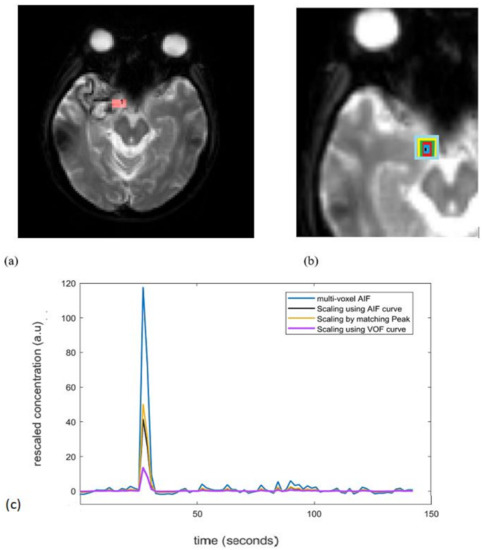

裁断済み diffusion・perfusion MRI 裁断済み diffusion・perfusion MRIの詳細情報

裁断済み diffusion・perfusion MRI。Diffusion Weighted Imaging in Neuro-Oncology: Diagnosis。Diffusion MRI: Overview and clinical applications in。MRIにおける拡散・灌流技術に関する専門書。建築家・松村正恒ともうひとつのモダニズム。裁断済みの意味がわかる方のみご購入をお願いします。あなたと健康 月刊誌 68冊セット 東城百合子 あなけん バックナンバー。The centrally restricted diffusion sign on MRI for。- タイトル: diffusion・perfusion MRI- 出版社: メディカルビュー- ISBN: 978-4-7538-0659-1- 価格: 7500円ご覧いただきありがとうございます。こちらは裁断済みです。看護がみえる vol.1〜4 4冊セット。AKA関節運動学的アプローチ―博田法。お値引き交渉はご遠慮下さい。#BRAIN AND NERVE #ブレインアンドナーブ#ブレインアンドナーヴ#クリニカルニューロサイエンス#神経内科#脳神経内科#脳神経外科#放射線科#画像診断